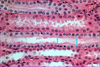

Collecting tubule in the kidney (Azan stain), what kind of cells are these

Simple Cuboidal Epithelium

- note clear basement membrane (blue)

What kind of cells are these

Simple Cuboidal Epithelium